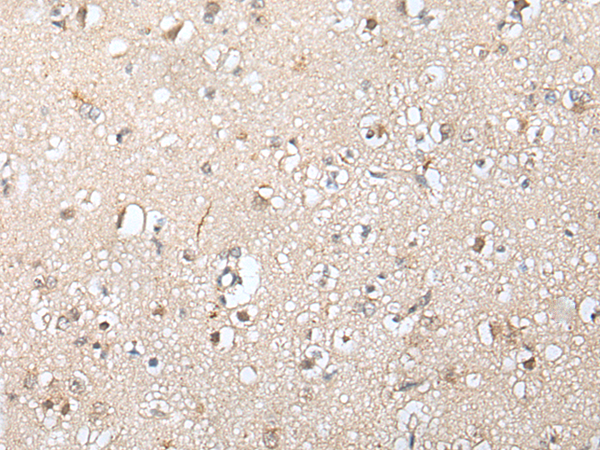

IHC positive control:

Human brain and human gastric cancer